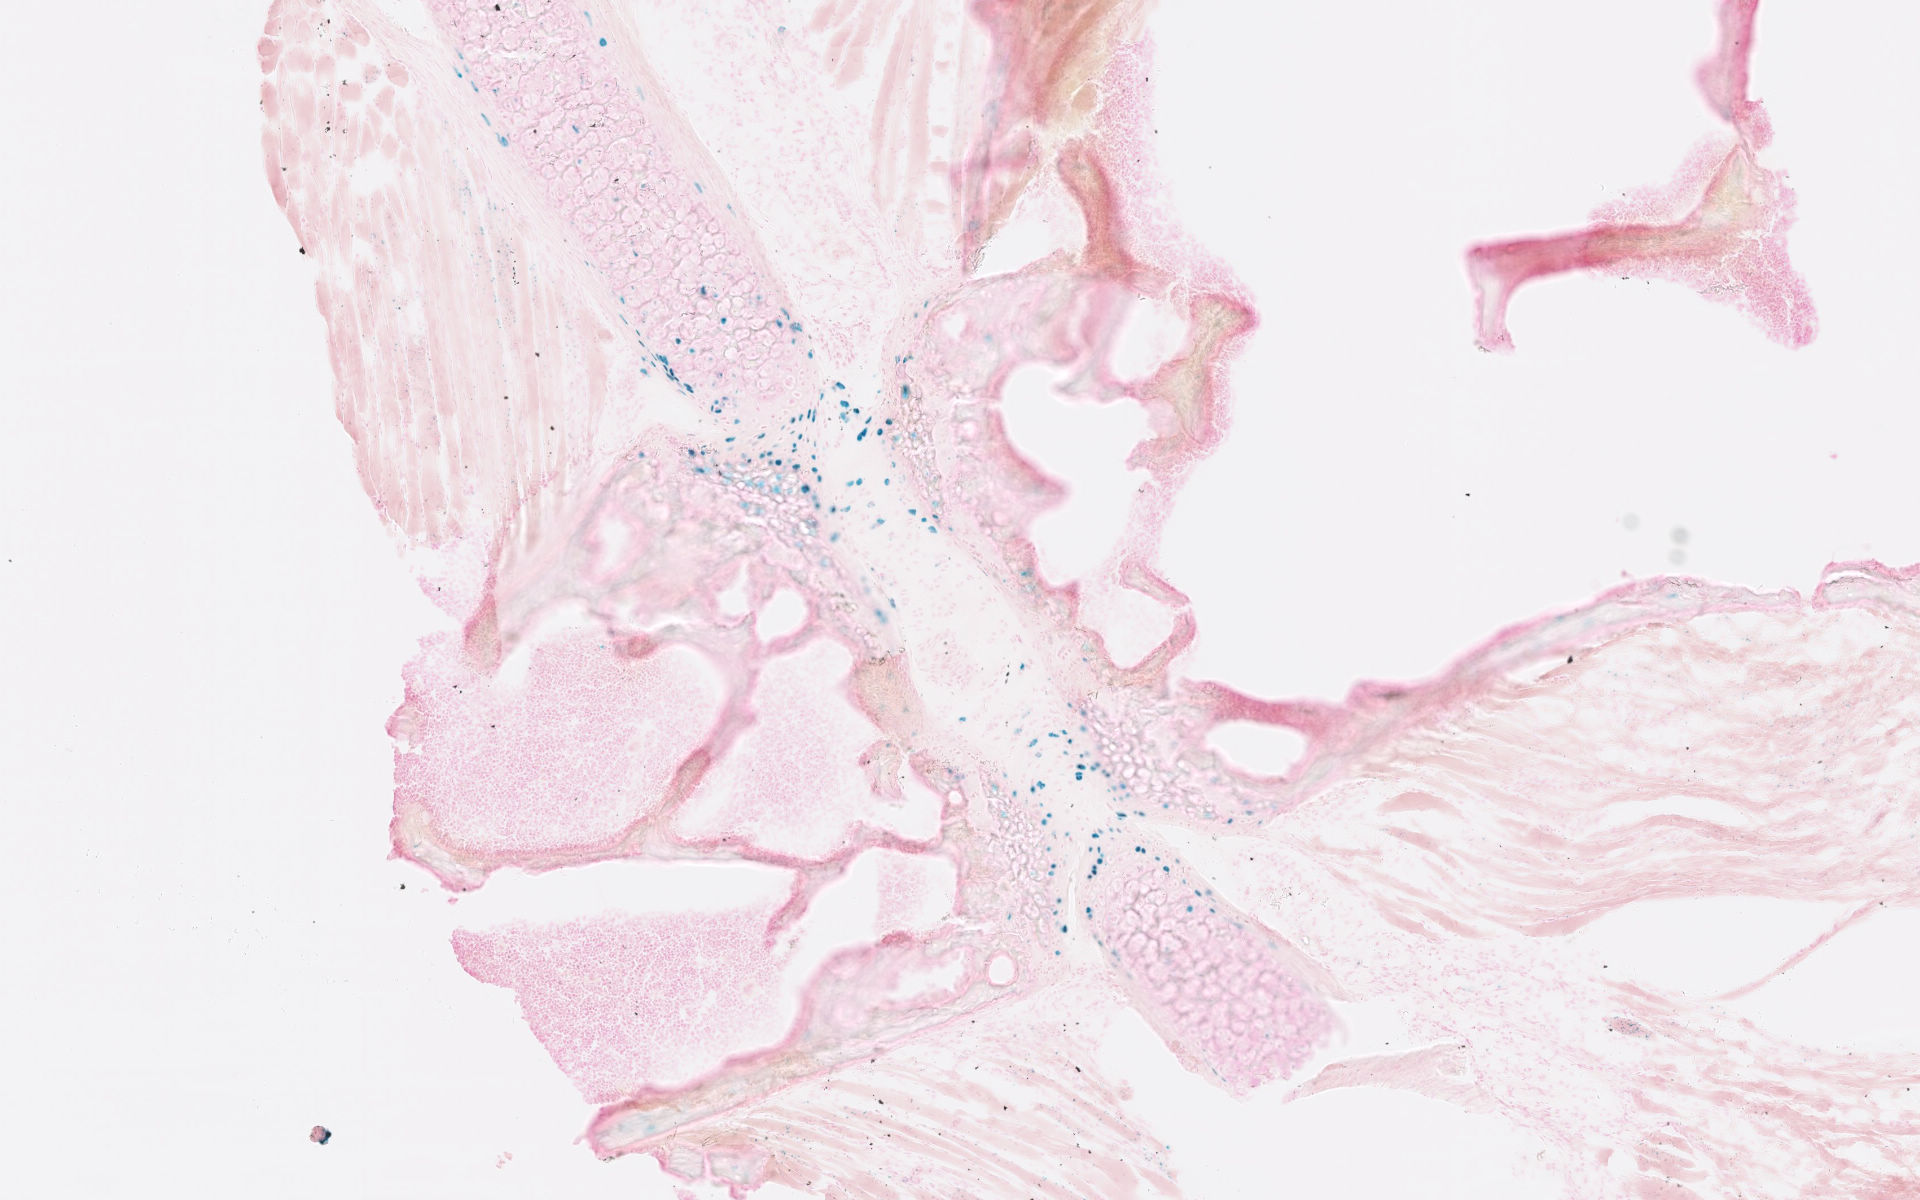

Images

Drag images to compare to others or to data in the table below. Drag corners to resize images for more detail.

Recombinase Activity

Result Notes